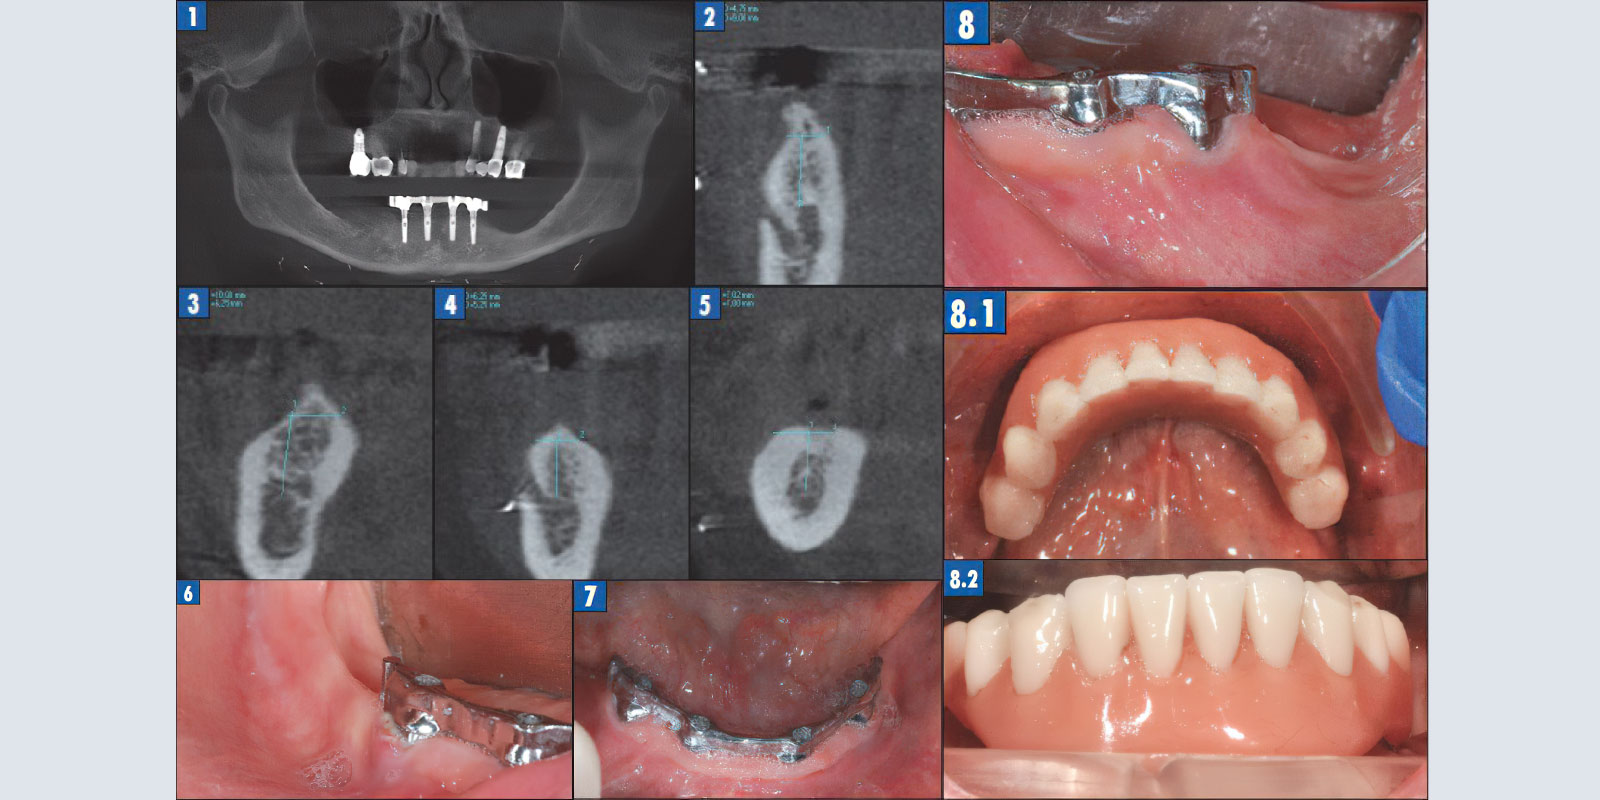

Пациентка Б. с полной адентией нижней челюсти в течение 7 лет использовала съемный бюгельный протез с фиксацией на титановой балке. Балка установлена на 4 имплантатах. Несколько раз она обращалась с просьбой установить ей еще несколько имплантатов с целью сделать протез на нижней челюсти несъемным, но ей было отказано в связи в редукцией твердых и мягких тканей в боковых участках нижней челюсти (рис. 1).

На рис. 2–5 представлены срезы компьютерной томограммы (КТ) в позициях 46, 47, 36, 37, где необходима установка имплантатов для фиксации несъемной конструкции. Видно, что ширина альвеолярного отростка в 4 квадранте составляет 4–6 мм при незначительном дефиците высоты в 1–2 мм, в 3 квадранте высота альвеолярного отростка составляет 6–7 мм при достаточной ширине. В данном клиническом случае мы имеем дело с критическим дефицитом твердых тканей вследствие чего имплантация без предварительной аугментации невозможна. Наряду с редукцией костной ткани полностью отсутствует прикрепленная кератинизированная десна (рис. 6–8).

На период хирургического лечения временной реставрацией служил бюгельный протез, у которого были удалены консольные части (рис. 8.1, 8.2).

Рис. 1. Компьютерная томография: на нижней челюсти с опорой на 4 имплантатах зафиксирована титановая балка.

Рис. 2. Позиция 46.

Рис. 3. Позиция 47.

Рис. 4. Позиция 36.

Рис. 5. Позиция 37.

Рис. 6. IV Квадрант.

Рис. 7. Фронтальный участок.

Рис. 8. III квадрант.

Рис. 8.1, 8.2. Временная реставрация.